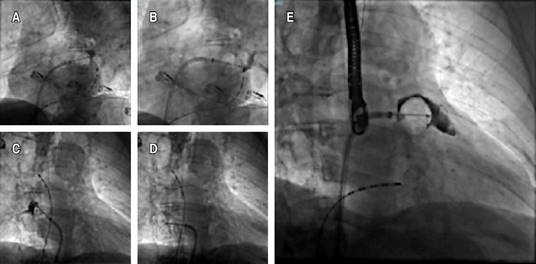

Even though conventional scores showed a low-risk result, it was considered essential to revert to sinus rhythm due to the strong thrombotic component conditioned by the UC and the contraindication for anticoagulation. An electrophysiological study was performed, followed by cryoablation of the four pulmonary veins (Figures 1 and 2), without achieving sinus rhythm, so it was decided to perform non-success electrical cardioversion twice (200 joules). The intervention team decided to perform a wide antral circumferential ablation (WACA) with posterior wall and left atrial appendage isolation, thus successfully achieving arrhythmia jugulation. Due to the hindrance of anticoagulation, after the left atrial appendage isolation, a closure device was placed in the left atrial appendage (Figures 2 and 3). After three months of optimal medical management with apixaban and amiodarone, the patient remained in sinus rhythm, and anticoagulation was discontinued. The patient is free of thrombotic and bleeding events for more than one year after the procedure and after stopping the anticoagulant.

Figure 3: Atrial appendage closure device sequence. A) Approach. B) Placement. C) Release.